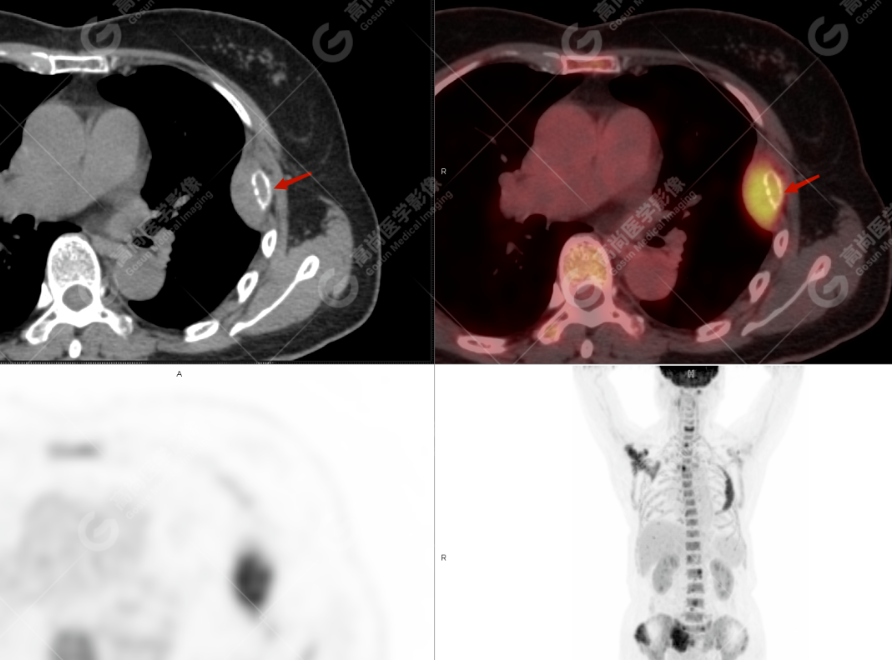

颅骨、寰椎前弓左侧份、第 6 颈椎、双侧肩胛骨(右侧为著)、左侧第 4 肋骨、第 1 胸椎、第 4 胸椎、第 2 腰椎及附件、第 4 腰椎及附件、骶骨、右侧髂骨、左侧坐骨结节、左侧股骨颈、双侧股骨小转子等均不同程度骨质吸收、破坏,其中右侧肩胛骨、左侧第 4 肋骨及骶骨右侧份软组织肿块影形成,上述病变均考虑恶性肿瘤(血液系统来源,多发骨髓瘤可能性大),建议右侧髂骨翼穿刺活检明确。

(4)PET-CT 影像表现:在溶骨性破坏区出现相重叠的 18F- FDG 高代谢区;通常呈弥漫性高代谢区。